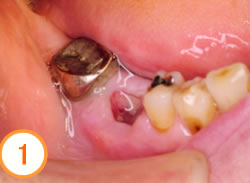

上の奥歯を抜歯しました。抜歯した部分の骨が無くなりくぼんでいます。

CTで調べるとインプラントを埋入する骨の量が足りません。 歯肉側の骨も失われていることがわかります。

歯肉側にはGBR法、上顎洞底部はソッケトリフトを併用して足りない骨を作ります

インプラント体が3本入りました